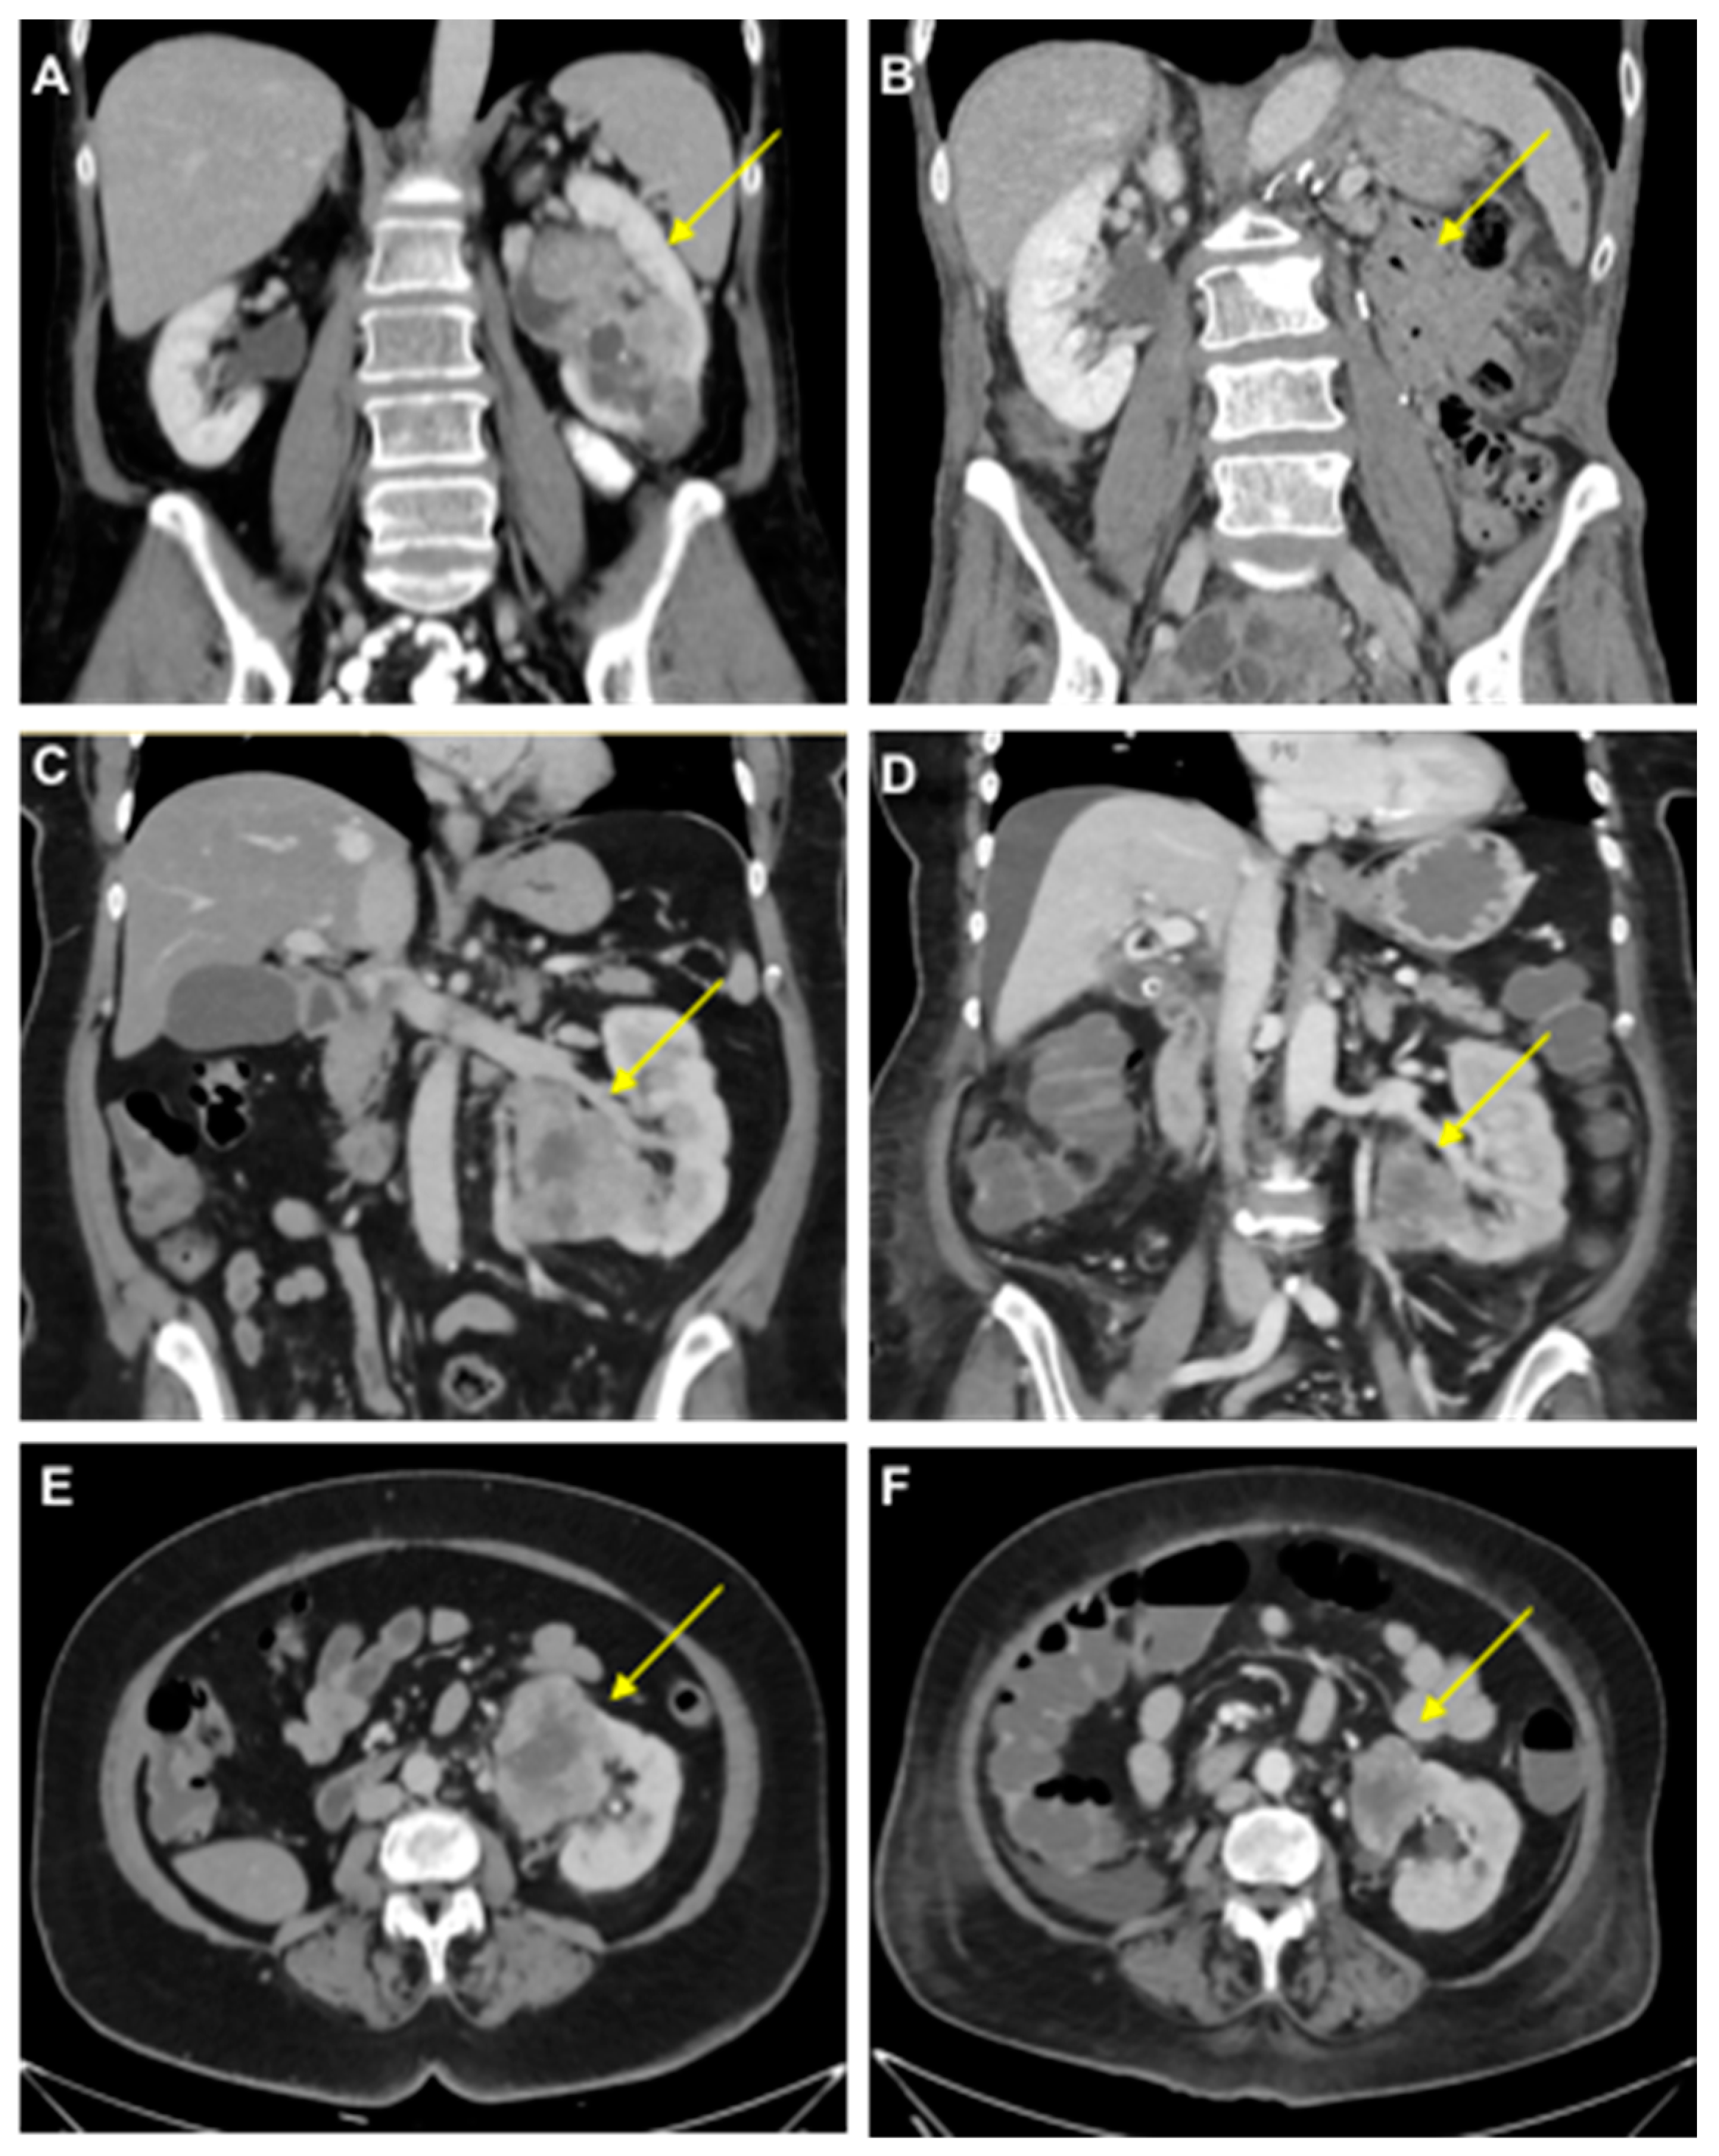

- Case study 1:

- Case study 2:

- Case study 3:

- Case study 4: